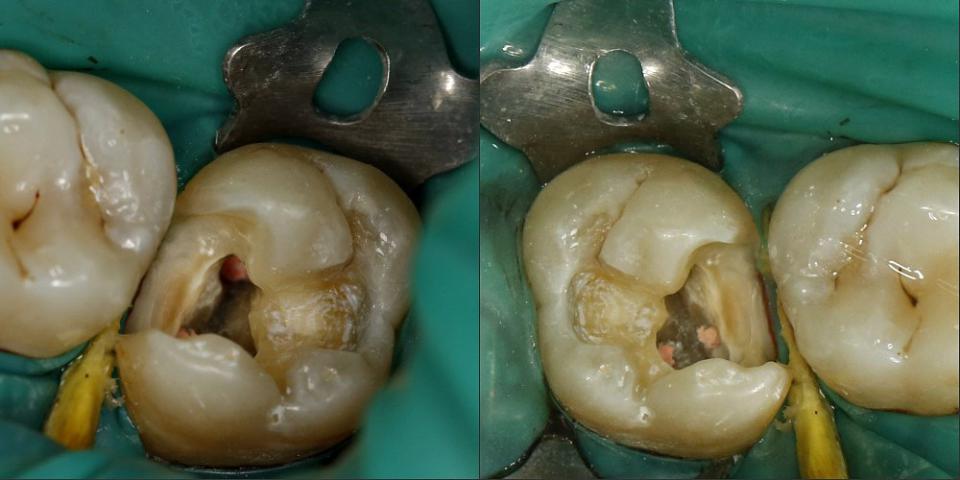

paraschyk1 Опубликовано 16 октября, 2015 Автор Опубликовано 16 октября, 2015 Выпал недавно реставрированный жевательный семерка вместе со штифтами. Т.е. там остались одни корни, над десной ничего от зуба нет. Было 2 штифта, реставрация + обычная простая коронка сверху. Все это аккуратно выпало. Один стоматолог говорит, что даже браться не будет, мол через годик снова отвалится, только вырывать. Другой говорит, что здоровый корень, какой нафиг рвать, только делать. Ниже вариант спасения зуба,когда полная жопа. Такой зуб может бегать пять лет и более.